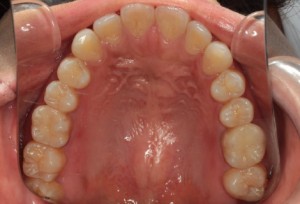

作成前

新規作成後の調整中